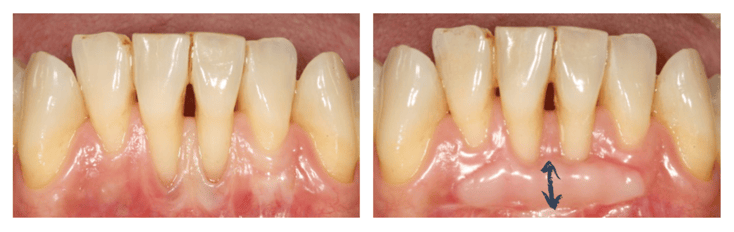

Greffe épithélio-conjonctive en regard d'une couronne dentaire prothétique © ParoSphère

Figure 1 - Greffe épithélio-conjonctive en regard d'une couronne dentaire prothétique © ParoSphère

L'objectif principal de cette technique n'est pas de recouvrir la partie de la racine dénudée mais de constituer un bandeau protecteur de gencive sous la récession. Cette technique n'est donc pas indiquée dans une zone esthétique. En revanche, elle est souvent utilisée pour renforcer la gencive autour de dents qui seront couronnées (Figure 1) ou pour stabiliser des récessions sur des dents du bas, non visibles lors du sourire (Figure 2).